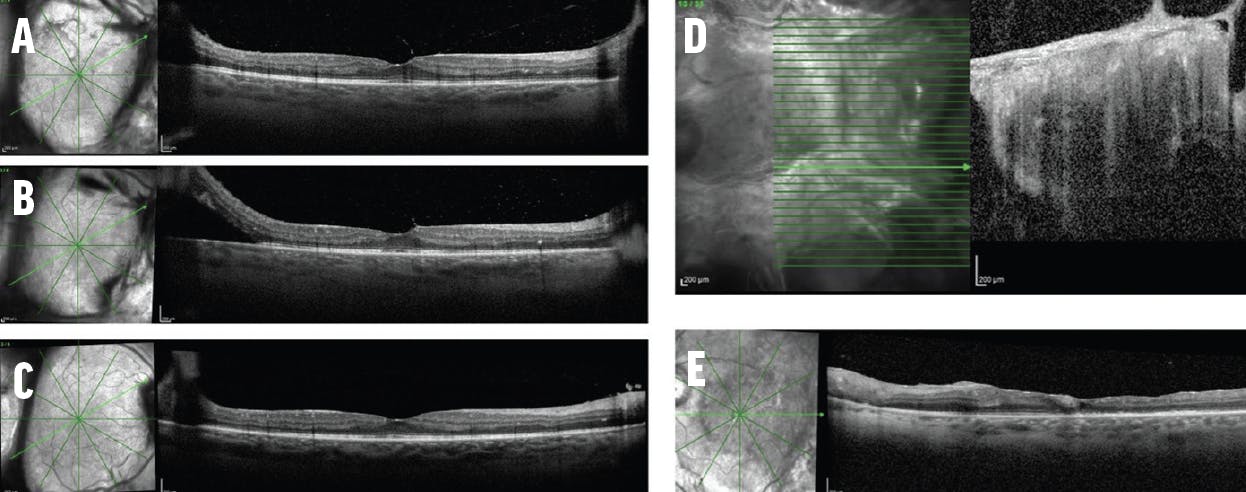

A 56-year-old phakic man presented with moderate nonproliferative DR (NPDR) in each eye and center-involving DME in his left eye (Figure 1). He had been diagnosed with type 2 diabetes 10 years prior, and his most recent hemoglobin A1c was 10.4. He reported blurry vision in his left eye for approximately 6 months.

<p>Figure 1. This 56-year-old man with moderate NPDR in each eye and center-involving DME in his left eye (A) did well with intravitreal anti-VEGF injections with resolution of the majority of the DME (B).</p>

Figure 1. This 56-year-old man with moderate NPDR in each eye and center-involving DME in his left eye (A) did well with intravitreal anti-VEGF injections with resolution of the majority of the DME (B).

The patient’s VA was 20/40 OS, and given the central location of the DME, I elected to treat with monthly injections of intravitreal bevacizumab (Avastin, Genentech/Roche). This may seem like a routine decision, but the patient’s entire clinical picture must be evaluated before settling on this approach: his type of diabetes, duration of the disease, most recent hemoglobin A1c, lens status, IOP, duration of symptoms, and any systemic comorbidities.

After 6 months of monthly bevacizumab injections, the patient’s VA improved to 20/25 OS, and he continues to receive intravitreal bevacizumab injections.